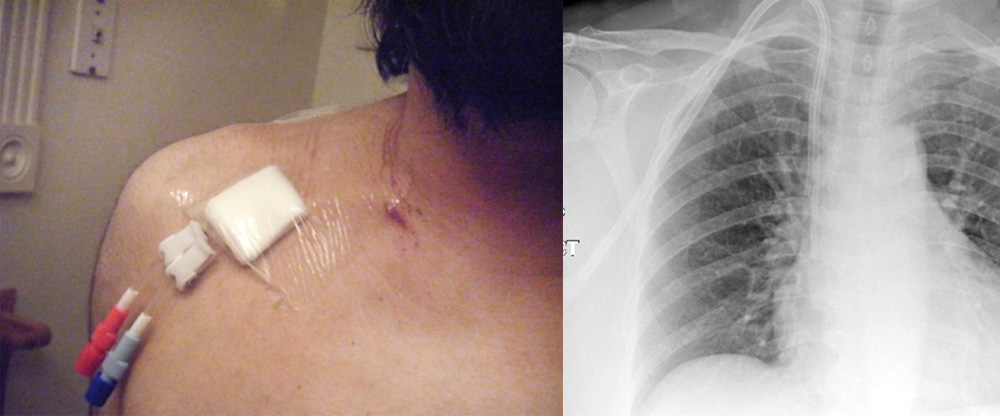

Dialysis is the only way to filter toxins & excess fluid in the body for these patients as they are suffering from long standing kidney disease- chronic kidney disease. A good venous access- catheterisation is required to get adequate dialysis. This can be through the neck veins or leg veins or through the fistula which is created surgically on the arm.

These catheter may face problems of reduced flow, blocks or infections and need to be watched carefully and replaced if required.